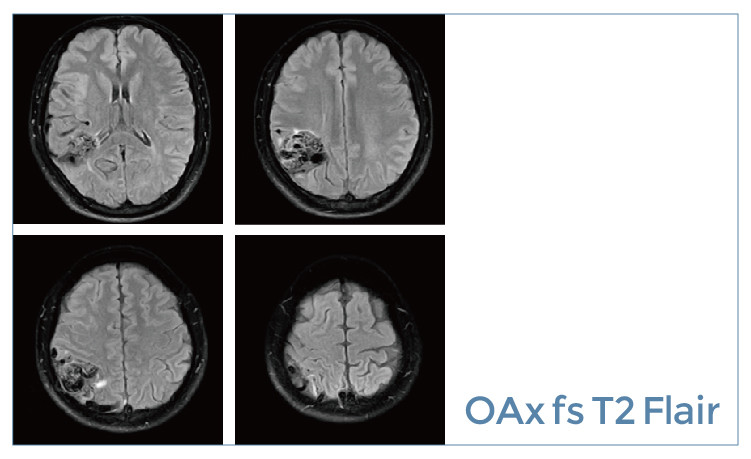

【朗润影像档案】20190531磁共振影像病例结果讨论